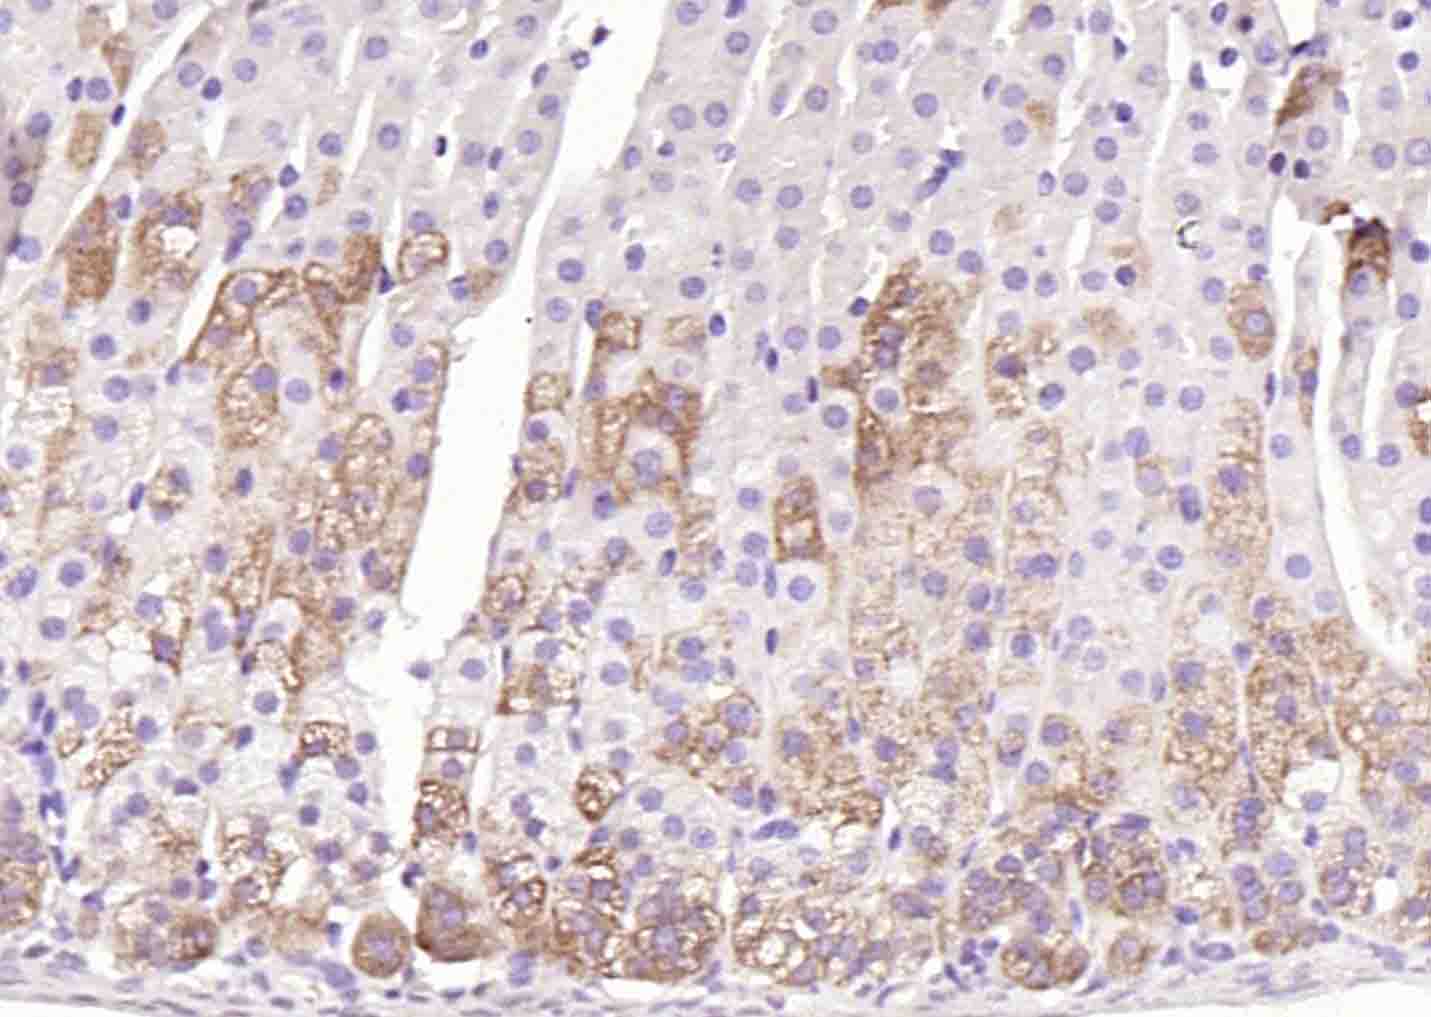

Paraformaldehyde-fixed, paraffin embedded (rat adrenal gland tissue); Antigen retrieval by boiling in sodium citrate buffer (pH6.0) for 15min; Block endogenous peroxidase by 3% hydrogen peroxide for 20 minutes; Blocking buffer (normal goat serum) at 37°C for 30min; Antibody incubation with (CYP11A1) Polyclonal Antibody, Unconjugated (bs-3608R) at 1:400 overnight at 4°C, followed by operating according to SP Kit(Rabbit) (sp-0023) instructionsand DAB staining.

Paraformaldehyde-fixed, paraffin embedded (mouse adrenal gland); Antigen retrieval by boiling in sodium citrate buffer (pH6.0) for 15min; Block endogenous peroxidase by 3% hydrogen peroxide for 20 minutes; Blocking buffer (normal goat serum) at 37°C for 30min; Antibody incubation with (CYP11A1) Polyclonal Antibody, Unconjugated (bs-3608R) at 1:200 overnight at 4°C, followed by operating according to SP Kit(Rabbit) (sp-0023) instructionsand DAB staining.

Paraformaldehyde-fixed, paraffin embedded (rat adrenal gland); Antigen retrieval by boiling in sodium citrate buffer (pH6.0) for 15min; Block endogenous peroxidase by 3% hydrogen peroxide for 20 minutes; Blocking buffer (normal goat serum) at 37°C for 30min; Antibody incubation with (CYP11A1) Polyclonal Antibody, Unconjugated (bs-3608R) at 1:200 overnight at 4°C, followed by operating according to SP Kit(Rabbit) (sp-0023) instructionsand DAB staining